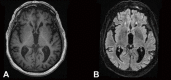

Case report: A 90-year-old male developed left hemichorea-hemiballismus after his second dose of the Pfizer-BioNTech COVID-19 vaccine. A wide range of investigations including magnetic resonance imaging did not reveal an alternative cause. [18F]-fluorodeoxyglucose-positron emission tomography (FDG-PET) showed increases in right putamen fixation compared to the left side. The patient showed significant improvement after five days of intravenous corticosteroids, with a normal FDG-PET.